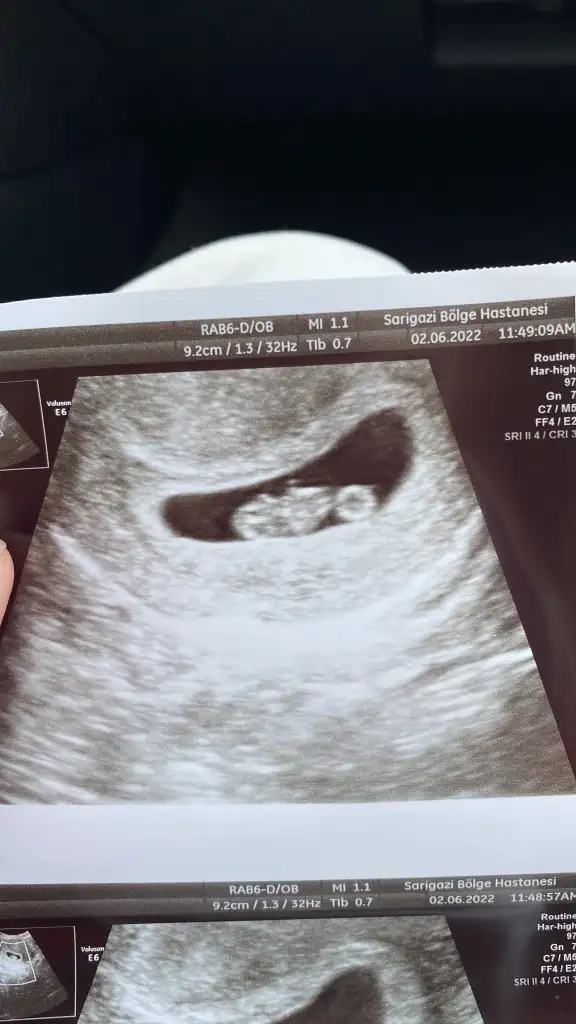

Buda bizim 7+2 görüntümüz 😊

Canim kucuk olan 8 haftalik vajinal buyuk olan 9 haftalik karindan